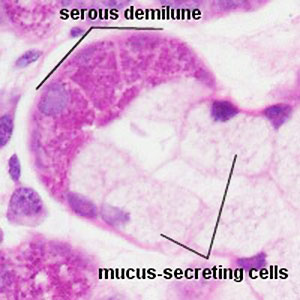

Histology

Submandibular gland

Mixed salivary gland, predominantly serous acini, some mucous acini with serous demilunes

- short intercalated ducts, and striated ducts c simple cuboidal lining epithelium

Sublingual gland

Mixed salivary gland, c predominantly mucous acini; some serous demilunes

- acini are composed of centrally-located mucous cells and peripheral serous demilunes